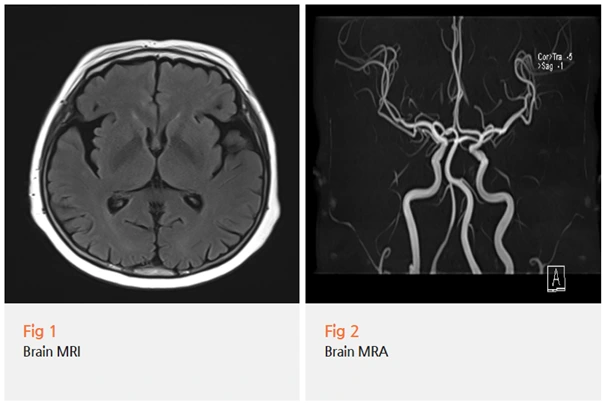

그래서 당일 뇌 MRI와 MRA 검사를 시행했습니다.

다행히 뇌에 다른 문제는 없었고,

임상 증상과 검사 결과를 종합해서 파킨슨병으로 진단할 수 있었습니다.